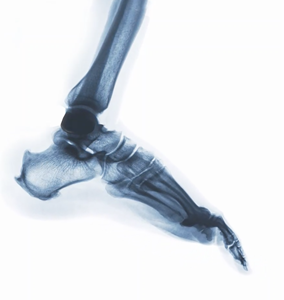

Two clinical areas where DDR can have an impact are in musculoskeletal (MSK) and thoracic imaging. DDR supports the diagnosis of MSK conditions by providing views of full patterns of articulatory mobility. Today, orthopedists rely on external motion and static X-ray to assess joint stability and spinal movement. With DDR, orthopedists and MSK specialists can acquire a full view of the MSK system in the supine and prone positions to view changes in the bone and articulations throughout the full range of motion. This information can be used to assess and monitor the spine and joints, such as the shoulder, knees, wrists and ankles, and enable the orthopedist or MSK specialist to provide a more detailed diagnosis quicker, reduce the need for additional imaging tests and enhance the quality of care.